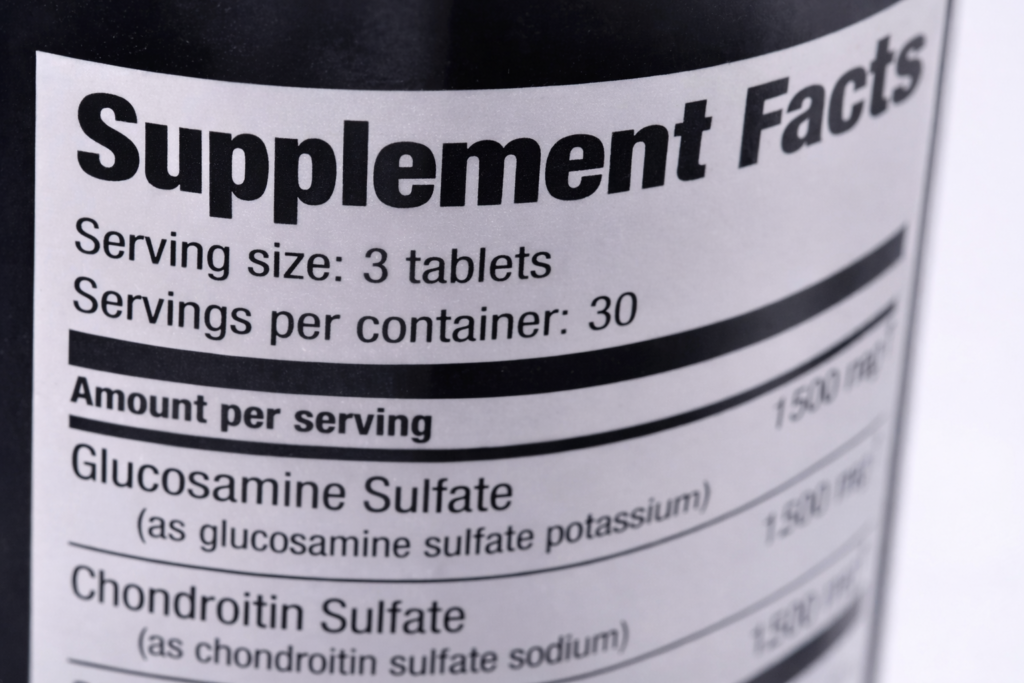

“Doc, I’ve tried everything. I take Glucosamine, Chondroitin, MSM, Turmeric. I use the $50 creams. But my knees still grind every time I stand up. Nothing works.”

I call this the “Supplement Graveyard.” It’s that cabinet in your kitchen filled with half-empty bottles. Every new bottle came with a flicker of hope… followed by the crushing disappointment three weeks later when you realized the stiffness was still there.

The supplement industry has been hiding a dirty little secret about those hard, white pills you’ve been swallowing for years.

There are two massive scientific reasons why they were doomed to fail you from the start.

Generic joint supplements are compressed into hard, chalky tablets or stuffed into cheap capsules. When you swallow them, they hit a pool of highly corrosive stomach acid.

Clinical studies show that up to 90% of the active ingredients in these pills are destroyed during digestion. The tiny fraction that survives is completely insufficient to repair decades of cartilage wear. You aren’t rebuilding your knees; you are quite literally flushing your money down the toilet.

😱 Failure #2: They Are “Single-Action” Band-Aids

Yet, most standard pills only contain 1 or 2 active ingredients based on outdated, “traditional” remedies rather than modern structural science.

1 or 2 ingredients can only provide a surface-level fix.